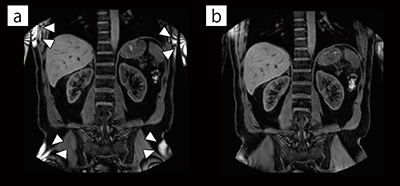

図5 mDIXON XDによる3D B0補正の効果

3D B0なし(a)に比べ3D B0補正あり(b)は,full FOV撮像においてストップバンドアーチファクトを低減することが可能である。